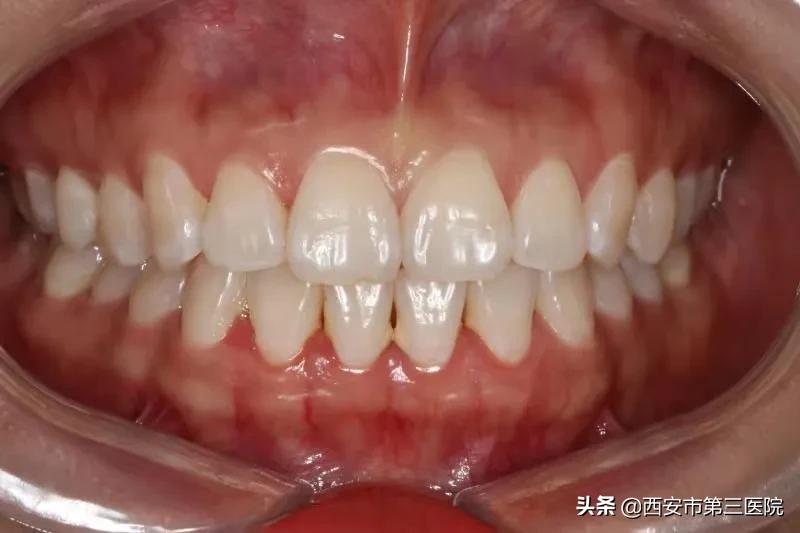

一、冷光美白

依赖于美白仪的一种美白方式,它不仅可以 去除牙齿表面的色素沉积,同时可进入牙齿深层达到脱色的效果。 根据临床实验表明,使用冷光牙齿美白技术,其效果可提高5-14个vita色阶,操作过程仅需三十分钟,无副作用,美白效果可维持两年以上。

美白前

美白后